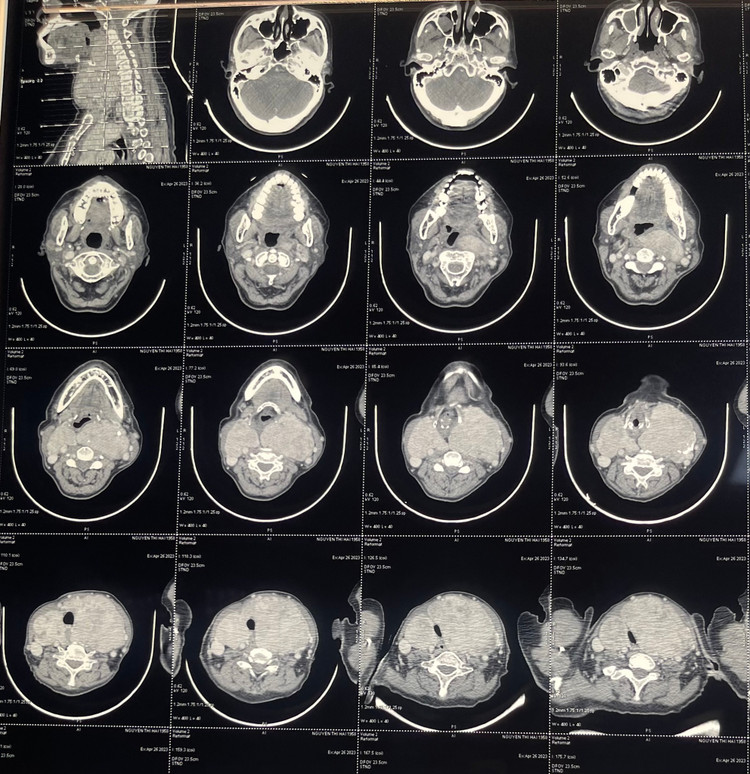

Bệnh nhân vào Bệnh viện TWQĐ 108 phát hiện bướu giáp khổng lồ, biến dạng vùng cổ. Chụp CT xác định bướu giáp rất to: kích thước thùy phải là 10x 6cm, thùy trái 12 x 7 cm, đè ép các tổ chức xung quanh, đè hẹp khí quản.

| Khối u khổng lồ gây chèn ép trên phim chụp |